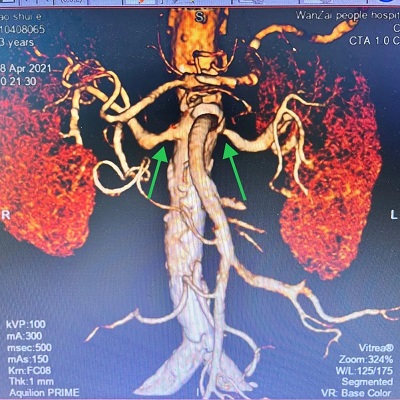

鲍阿姨的肾动脉CTA影像

肾动脉CTA结果可见鲍阿姨的双肾动脉都有狭窄,特别是左肾动脉开口“堵”得很严重,这才是引起她血压升高的罪魁祸首,这种情况服用降压药是很难控制的。如果再继续发展下去,还会导致肾功能不全,甚至肾功能衰竭。